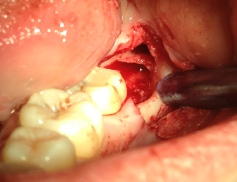

ΧΕΙΡΟΥΡΓΙΚΗ ΕΠΙΜΗΚΥΝΣΗ ΜΥΛΗΣ ΔΟΝΤΙΩΝ ΠΡΙΝ ΤΗΝ ΠΡΟΣΘΕΤΙΚΗ ΑΠΟΚΑΤΑΣΤΑΣΗ

ΠΡΙΝ